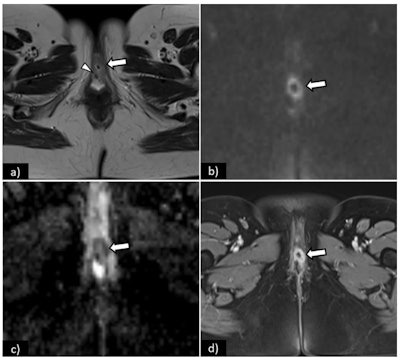

(a) Schematic illustration of International Federation of Gynaecology and Obstetrics (FIGO) stage I. Axial T2-weighted image (b), axial fat saturation T2-weighted image (c) and diffusion-weighted imaging with b-value = 800 s/mm2. (d) shows a vulvar tumor measuring < 2 cm, with pathologic proven stromal invasion of 4 mm, corresponding to FIGO stage IB. All images courtesy of Dr. Olivera Nikolić and Insights into Imaging."In spite of that, MRI staging of vulvar cancer is not used routinely in all cancer centres," the group's chair, Dr. Olivera Nikolić of the University of Novi Sad, Serbia, and colleagues wrote in an article published on 22 September in Insights into Imaging. "Standardising image acquisition techniques and MRI interpretation reduces ambiguity and ultimately improves the contribution of radiology to the staging and management of patients with vulvar cancer."